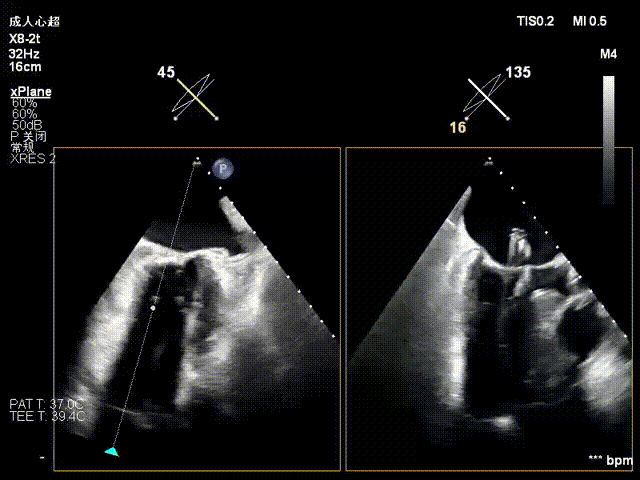

术前经食道超声显示:二尖瓣C1、P1区脱垂,重度关闭不全,彩色多普勒提示大量二尖瓣反流。术前瓣口面积MVA约5cm²,瓣环前后径AP约36.9mm,前叶A1约26mm,后叶P1约15.2mm。

患者全麻后仰卧位,常规消毒铺巾,置入下食道超声探头。于左前胸第五肋间做小切口,暴露心尖,全身肝素化后,心尖穿刺,逐步送入二尖瓣夹系统。术中在超声引导下,分别于C1及A1/P1区植入2枚ValveClamp®二型(MVC-Ⅱf)二尖瓣夹,夹合后超声显示二尖瓣反流明显减轻,随即释放夹子。术后置左侧胸腔引流管1根,逐层关闭胸壁,患者顺利转入ICU观察。

术后复查超声心动图显示:二尖瓣轻度返流,三尖瓣中度返流,二尖瓣可见金属夹回声,启闭正常;各心室大小正常,升主动脉不宽,主瓣回声增强,启闭良好;二尖瓣舒张期峰值流速1.4 m/s,功能面积2.1 cm²,跨瓣平均压差约4 mmHg。